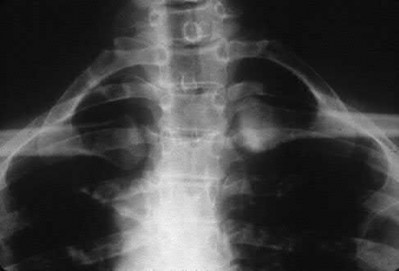

For a patient with an unstable pelvic fracture, the amount of blood tranfusions required in the first 24 hours has shown to be most predictive for what variable?

Unstable pelvic fractures can be devastating injuries often resulting in significant morbidity and even death.

According to the referenced study by Smith et al, fracture pattern and angiography/embolization were not predictive of mortality in patients with unstable pelvic injuries. The three factors they found to be predictive were: increased blood transfusions in the first 24 hours, age >60 years, and increased ISS or RTS scores. Deaths were most commonly from exsanguination (24 hours).